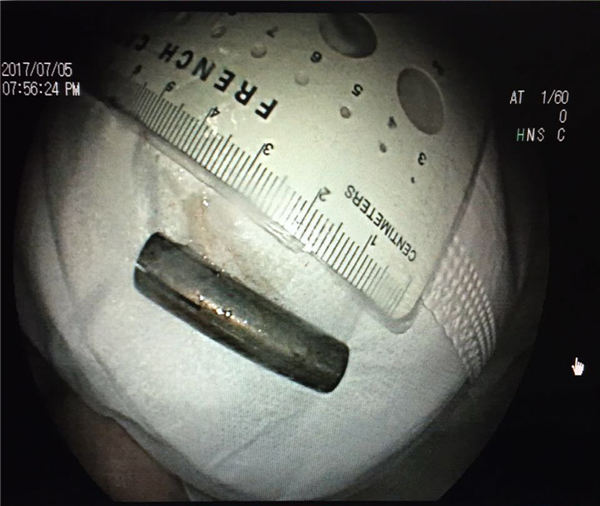

经联系,消化科殷军社医生和胃镜室工作人员紧急返院手术,医护通力协作,小心操作,终于成功将食管内的异物取出。之后,鉴于安全考虑,将女孩儿转入ICU密切观察治疗,随后女孩意识逐渐清醒,脱离了危险。

经查,异物是一个长约4厘米、直径约1厘米的管状金属物。